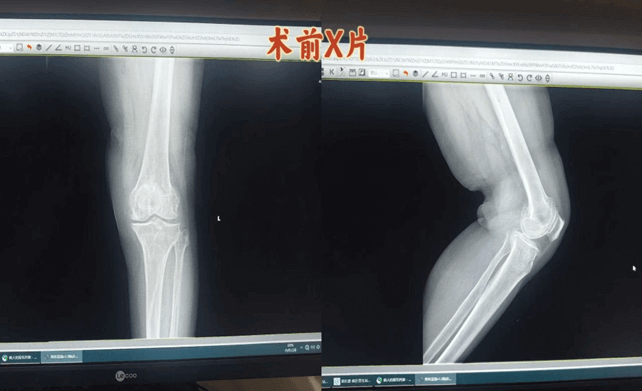

案例:患者女,69岁,系“反复左膝关节疼痛10余年,加重伴行走受限1月”入住我科。